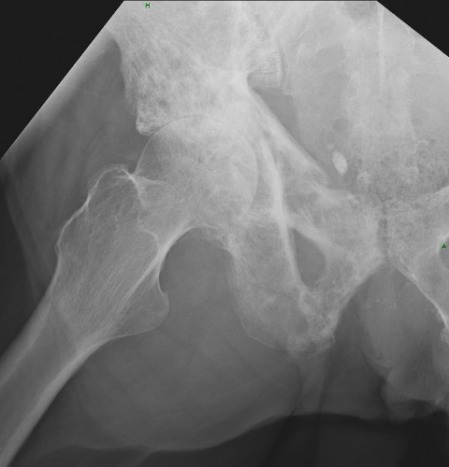

1. What are the main findings?

2. What are the differential considerations for the key finding?

3. What disorders most commonly produce a sclerotic Kohler's teardrop sign?